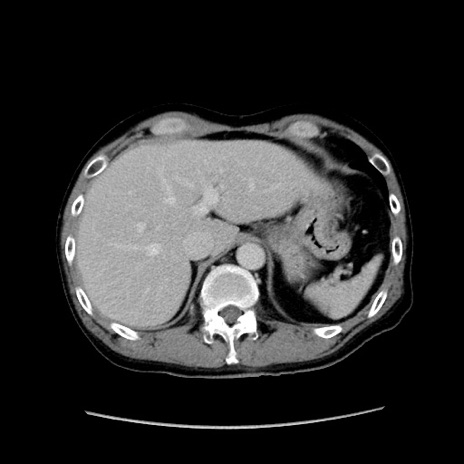

症例37(横断像)

【症例】40歳代 男性

【主訴】腹痛

【現病歴】4時間ほど前に電車に乗車中に臍部上より腹痛出現。徐々に増悪し起立困難となり、救急外来受診。生ものは数日食べていない。今朝お雑煮を食べた。

【身体所見】BT 36.8℃、BP 117/84mmHg、HR 91/min、SpO2 97%、苦悶様、腹部:臍上部広範囲圧痛あり、反跳痛±

【データ】WBC 8100、CRP 0.03